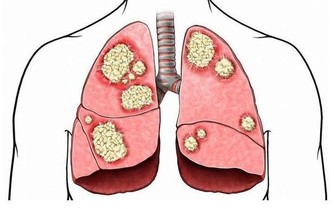

人體50%的骨骼和肌肉都在兩條腿上,人一生中70%的活動和能量消耗都要由它完成;

兩條腿上有人體50%的神經及血管,流淌著50%的血液,是連接身體的大循環組織。